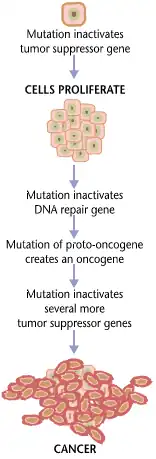

Cancer is fundamentally a disease of tissue growth regulation. For a normal cell to transform into a cancer cell, the genes that regulate cell growth and differentiation must be altered.[99]

The affected genes are divided into two broad categories. Oncogenes are genes that promote cell growth and reproduction. Tumor suppressor genes are genes that inhibit cell division and survival. Malignant transformation can occur through the formation of novel oncogenes, the inappropriate over-expression of normal oncogenes, or by the under-expression or disabling of tumor suppressor genes. Typically, changes in multiple genes are required to transform a normal cell into a cancer cell.[100]

Genetic changes can occur at different levels and by different mechanisms. The gain or loss of an entire chromosome can occur through errors in mitosis. More common are mutations, which are changes in the nucleotide sequence of genomic DNA.

Large-scale mutations involve the deletion or gain of a portion of a chromosome. Genomic amplification occurs when a cell gains copies (often 20 or more) of a small chromosomal locus, usually containing one or more oncogenes and adjacent genetic material. Translocation occurs when two separate chromosomal regions become abnormally fused, often at a characteristic location. A well-known example of this is the Philadelphia chromosome, or translocation of chromosomes 9 and 22, which occurs in chronic myelogenous leukemia and results in production of the BCR-abl fusion protein, an oncogenic tyrosine kinase.

Small-scale mutations include point mutations, deletions, and insertions, which may occur in the promoter region of a gene and affect its expression, or may occur in the gene's coding sequence and alter the function or stability of its protein product. Disruption of a single gene may also result from integration of genomic material from a DNA virus or retrovirus, leading to the expression of viral oncogenes in the affected cell and its descendants.

Replication of the data contained within the DNA of living cells will probabilistically result in some errors (mutations). Complex error correction and prevention are built into the process and safeguard the cell against cancer. If a significant error occurs, the damaged cell can self-destruct through programmed cell death, termed apoptosis. If the error control processes fail, then the mutations will survive and be passed along to daughter cells.

Some environments make errors more likely to arise and propagate. Such environments can include the presence of disruptive substances called carcinogens, repeated physical injury, heat, ionising radiation, or hypoxia.[101]

The errors that cause cancer are self-amplifying and compounding, for example:

- A mutation in the error-correcting machinery of a cell might cause that cell and its children to accumulate errors more rapidly.

- A further mutation in an oncogene might cause the cell to reproduce more rapidly and more frequently than its normal counterparts.

- A further mutation may cause the loss of a tumor suppressor gene, disrupting the apoptosis signaling pathway and immortalizing the cell.

- A further mutation in the signaling machinery of the cell might send error-causing signals to nearby cells.

The transformation of a normal cell into cancer is akin to a chain reaction caused by initial errors, which compound into more severe errors, each progressively allowing the cell to escape more controls that limit normal tissue growth. This rebellion-like scenario is an undesirable survival of the fittest, where the driving forces of evolution work against the body's design and enforcement of order. Once cancer has begun to develop, this ongoing process, termed clonal evolution, drives progression towards more invasive stages.[102] Clonal evolution leads to intra-tumour heterogeneity (cancer cells with heterogeneous mutations) that complicates designing effective treatment strategies and requires an evolutionary approach to designing treatment.